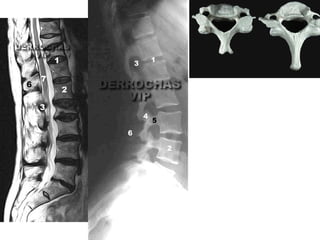

El documento describe los principales sistemas del cuerpo humano, incluyendo el sistema óseo, sistema respiratorio, sistema cardiovascular, sistema nervioso y los órganos de los sentidos como el oído y la vista.